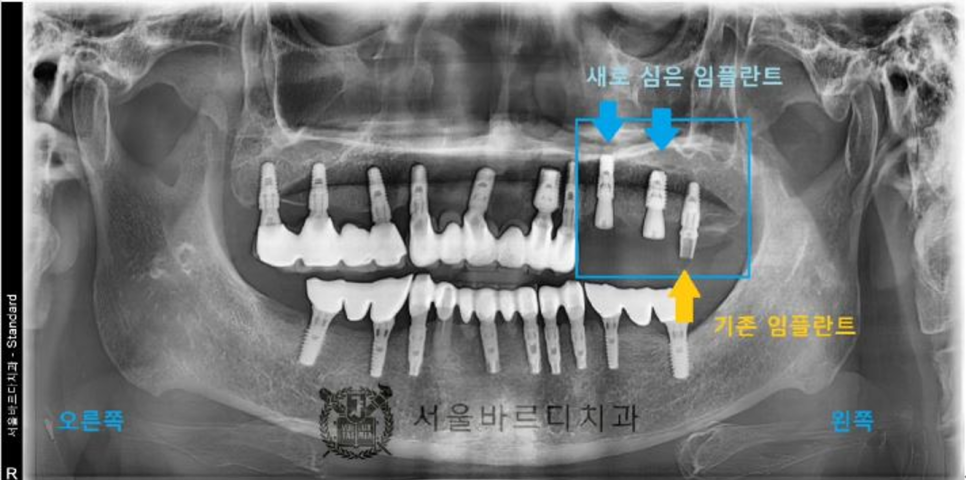

빠진 임플란트와 그 옆에 하나 더 임플란트 시술을 하셨습니다.

임플란트 후에도 수술이 잘 되었는지

파노라마와 3D CT촬영으로 결과를 확인합니다.

20230825

이제 3개월 정도 뼈와 임플란트가 붙는 기간동안 기다려야합니다.

20231027

뼈와 임플란트가 잘 붙었으면

이제 보철물을 제작합니다.

기존 보철물보다 임플란트 한 개를 더 추가하여

총 4개의 치아를 회복시켜드렸습니다.

임플란트는 뿌리 부분이 가늘고 머리가 크기 때문에

힘을 더 잘 받기 위해 4개의 치아를 묶어서 제작하였습니다.

4개의 치아를 묶어드려야 더 튼튼하고

음식물도 끼지 않기 때문에

최대한 오래 오래 쓰실 수 있는 방법이었습니다.